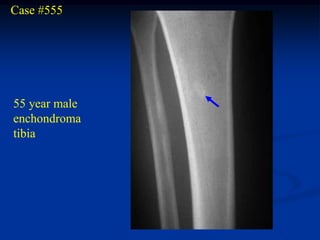

Case #555

55 year male

enchondroma

tibia

Bone scan

Coronal T-1 MRI

Coronal T-2 MRI

tumor

Biopsy photomic